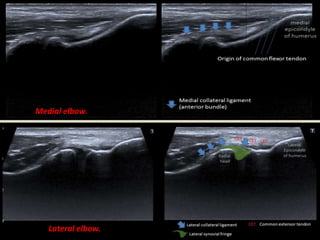

Medial elbow.

Lateral elbow.